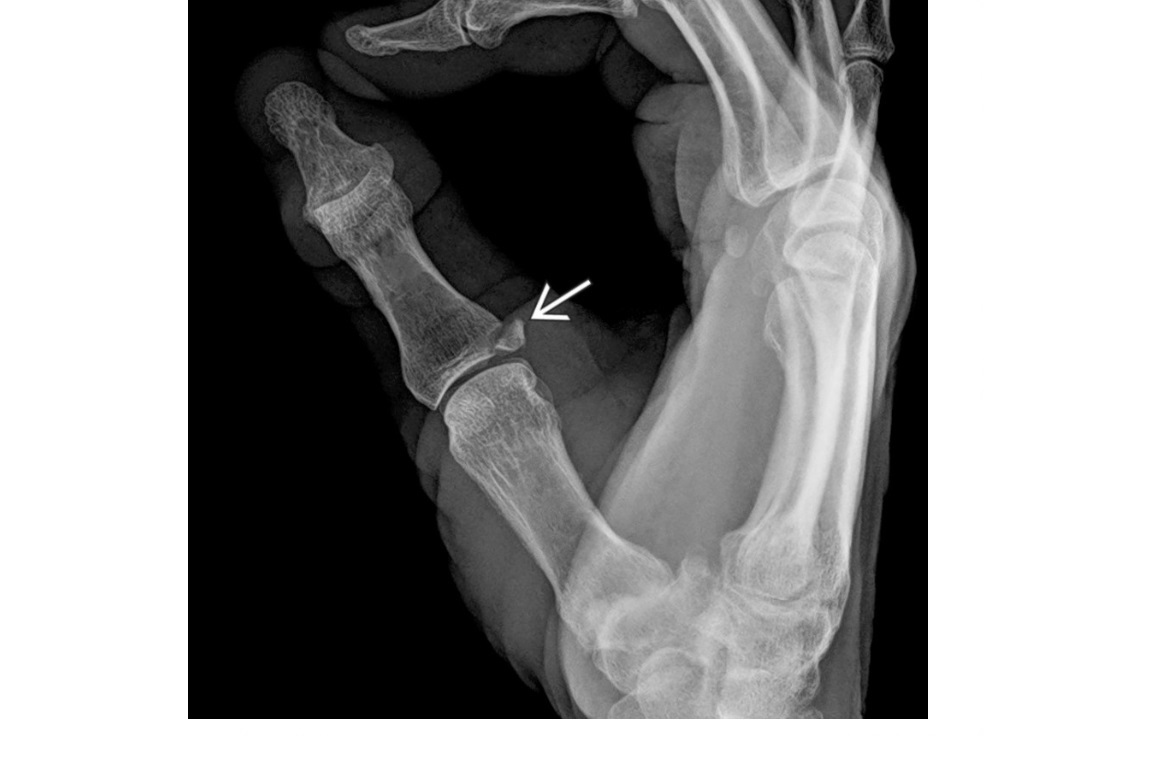

Gamekeepers

Avulsion fracture of the base of the proximal first phalanx

Ulnar collateral ligament disruption

STENER lesion = when adductor tendon gets caught in the torn edges of the UCL = Surgery